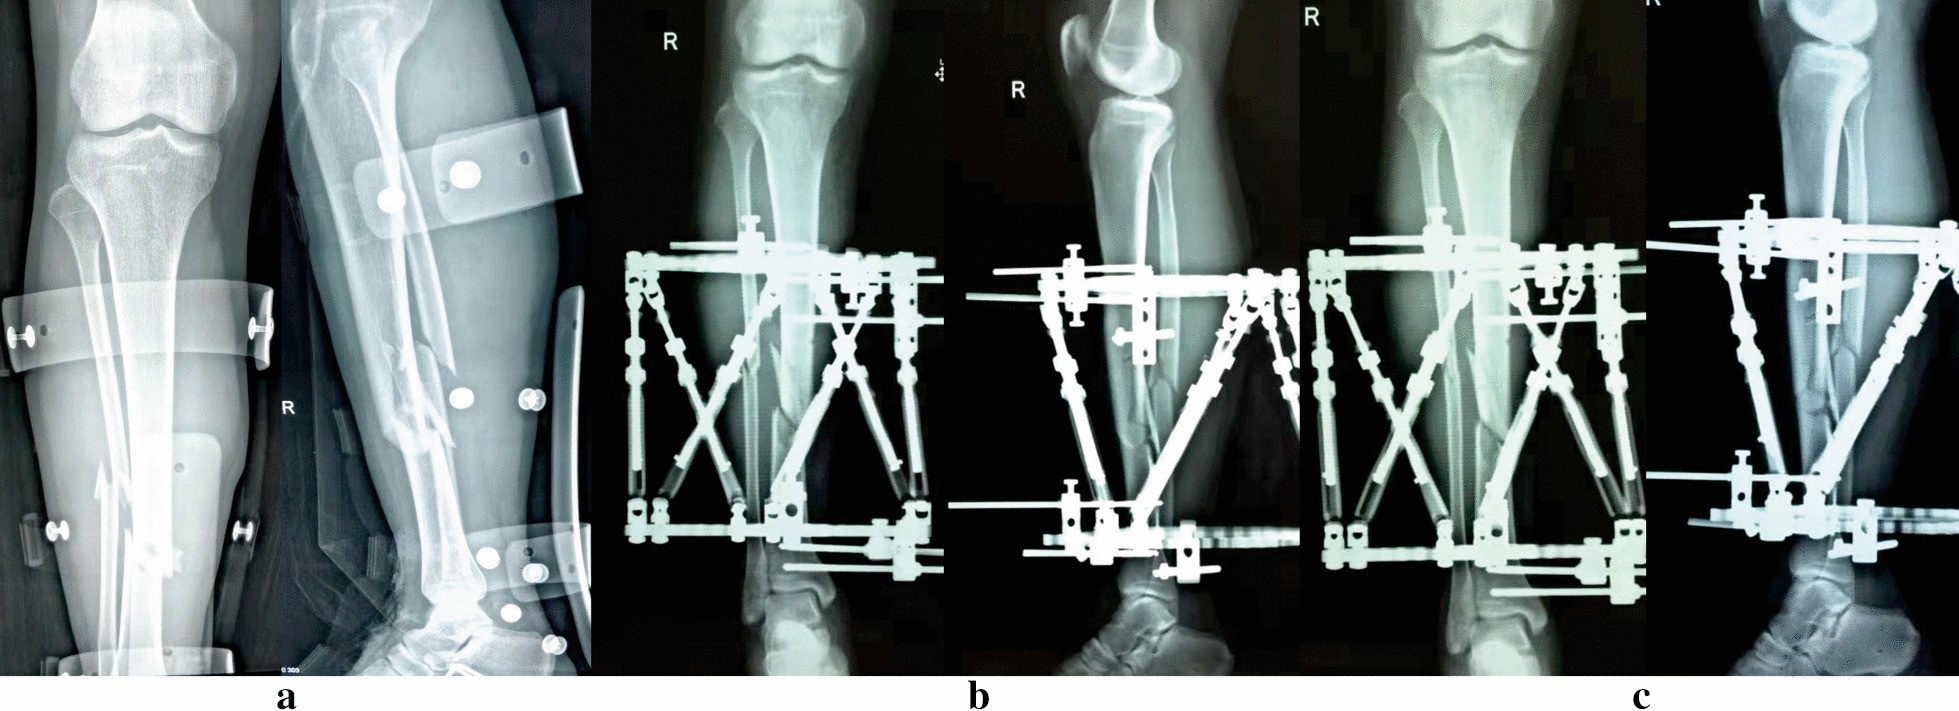

Images of a 32-year-old man suffered posttraumatic open tibial and fibular fractures treated by the TSF. a Posttraumatic AP and lateral views of X-rays. b Radiographs immediately after application of TSF. c Radiographs after final correction